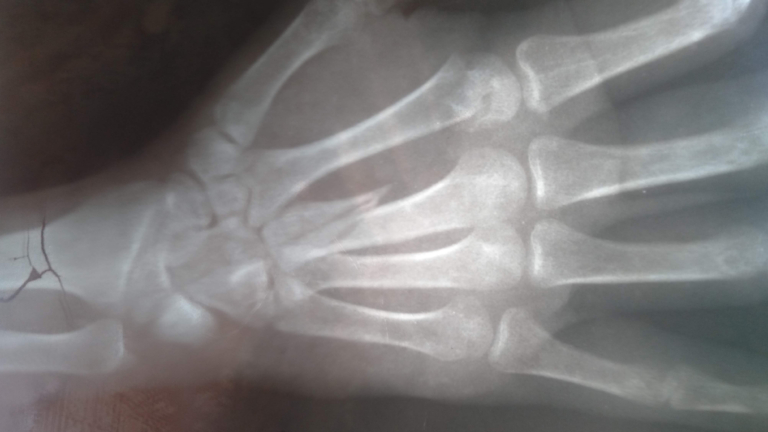

De gladheid heeft het afgelopen weekend voor honderden botbreuken gezorgd in Noord-Holland. Dat blijkt uit een rondgang van mediapartner NH Nieuws langs de ziekenhuizen.

Vrijwel alle botbreuken ontstonden bij valpartijen door de gladheid. Het aantal botbreuken dat bij het schaatsen is opgelopen lijkt erg klein.